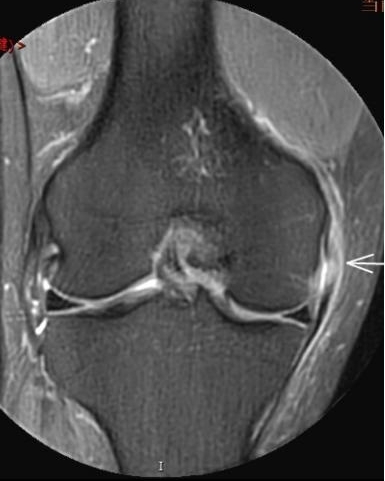

3. 上下樓“針刺痛”——軟骨的“磨砂紙預(yù)警”

場景:爬樓梯時膝蓋刺痛,久坐后僵硬如“生銹齒輪”

MRI偵查:發(fā)現(xiàn)軟骨變薄、缺損(早期骨關(guān)節(jié)炎信號),趕在“路面塌方”前修復(fù)

(軟骨損傷)